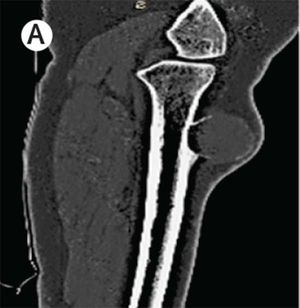

A 29-year-old female patient with known type 2 diabetes presented with complaints of pain and swelling of the left leg for a few months. Clinical examination revealed a tender palpable mass on the antero-medial aspect of her tibia with no restriction in range of motion or neurovascular compromise. What is the most likely diagnosis? A)Periosteal chondroma B)Periosteal Ewing’s sarcoma C)Periosteal aneurysmal bone cyst D)Periosteal metastatic lesion (primary lung)

Periosteal aneurysmal bone cyst....? Lesion in the radiograph show cystic....